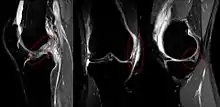

The unhappy triad, also known as a blown knee among other names, is an injury to the anterior cruciate ligament, medial collateral ligament, and meniscus. Analysis during the 1990s indicated that this 'classic' O'Donoghue triad is actually an unusual clinical entity among athletes with knee injuries. Some authors mistakenly believe that in this type of injury, "combined anterior cruciate and medial collateral ligament (ACL- MCL) disruptions that were incurred during athletic endeavors" always present with concomitant medial meniscus injury. However, the 1990 analysis showed that lateral meniscus tears are more common than medial meniscus tears in conjunction with sprains of the ACL.[1]

The unhappy triad occurs due to a lateral blow to the knee causing a rupture in the anterior cruciate ligament, medial collateral ligament, and meniscus. Injury is most often sustained when a lateral (from the outside) force impacts the knee while the foot is fixed on the ground. The strong valgus or rotary force to the knee tears the ACL, MCL, and medial meniscus all together. This type of injury occurs often in contact sports such as football, rugby, or motocross. During the injury, the leg is laterally rotated and over-abducted. In about 10% of cases, the force is applied to the opposite side of the knee, and the lateral and posterolateral ligaments are torn.

Injury to the medial meniscus is about five times greater than injury to the lateral meniscus due to its anatomical attachment to the MCL.[8] Lateral meniscal tears are more common in acute ACL injuries, whereas medial mensical injuries are more common in chronic ACL-deficient knees and more amenable to repair.[9]

Meta-analysis shows that in acute injuries of the ACL associated with a meniscus tear, 44% were of the medial meniscus, whereas 56% were of the lateral meniscus; in chronic ACL insufficiency, 70% were medial whereas 30% were lateral.[10]